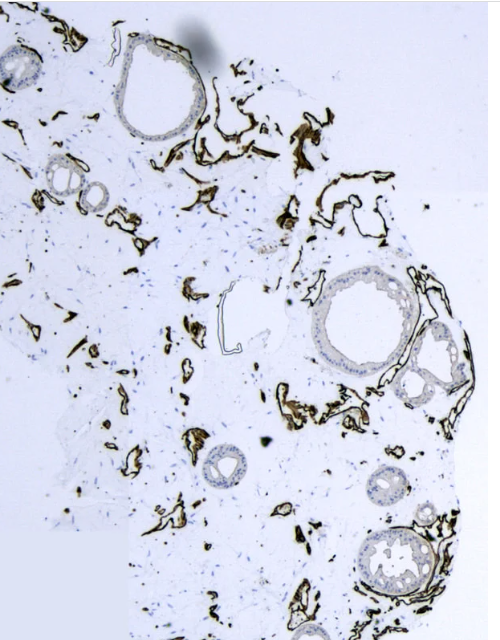

尽管3D器官模型提供了复杂性和结构性成熟,但它们缺乏血管形成和灌注限制了这些模型有效地概括器官生理学的能力。设计了一个名为 IFlowPlate 的微流控平台,可用于在体外培养多达 128 个立灌注和血管化的结肠类器官。与传统的微流体设备不同,具有“露天”设计的血管化器官芯片装置不需要任何外部抽水系统,并且允许组织提取下游分析,例如组织化学甚至体内移植。通过优化细胞外基质(ECM)和培养基的配方,患者衍生的结肠器官在自组装的血管网络中成功培养,并发现在恒定灌注下,结肠机可以在平台中增长更好与传统的静态条件相比。此外,使用该平台开发了具有先天免疫功能的结肠炎症模型,其中可以从脉管系统招募循环单核细胞,分化为巨噬细胞,并渗透结肠类器官以响应肿瘤坏死因子(TNF)-炎症细胞因子的刺激。凭借在血管内灌注下生长血管化结肠类器官的能力,IFlowPlate 平台可以为筛选潜在治疗靶点或建模相关疾病带来新的可能性。

2、具有可灌注脉管系统的结肠类器官

使用Iflowplate?发现器官研究的未来,这是我们创新的微流体平台,旨在克服传统的3D器官模型的局限性。IFlowPlate? 能够在体外培养多达 128 个立灌注和血管化的结肠类器官,

从而更准确地表示器官生理学。

image.png

与传统的微流体装置不同,我们特的“开放式”设计消除了对外部泵系统的需求,并且可以轻松提取组织以进行下游分析,例如组织化学或体内移植。

通过优化细胞外基质 (ECM) 和培养基配方,IFlowPlate? 成功地在自组装血管网络内共培养患者来源的结肠类器官。与传统静态条件相比,我们的平台已被证明可以显着改善器官生长。

IFlowPlate? 还可以利用先天免疫功能对结肠炎症进行建模。循环单核细胞可以从脉管系统中招募,分化为巨噬细胞,并响应 TNF-α 炎症细胞因子的刺激而渗透结肠类器官。